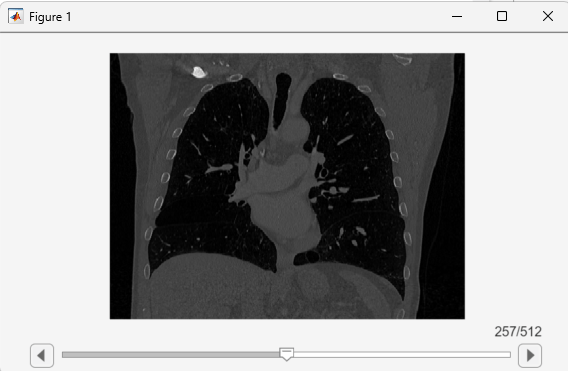

When it opens a figure, the sliceViewer object displays the middle image

in the stack. The viewer displays slices along the primary direction of the volume, specified

by the Orientation property of the medicalVolume object.

Use the slider to navigate through the volume and view individual slices.